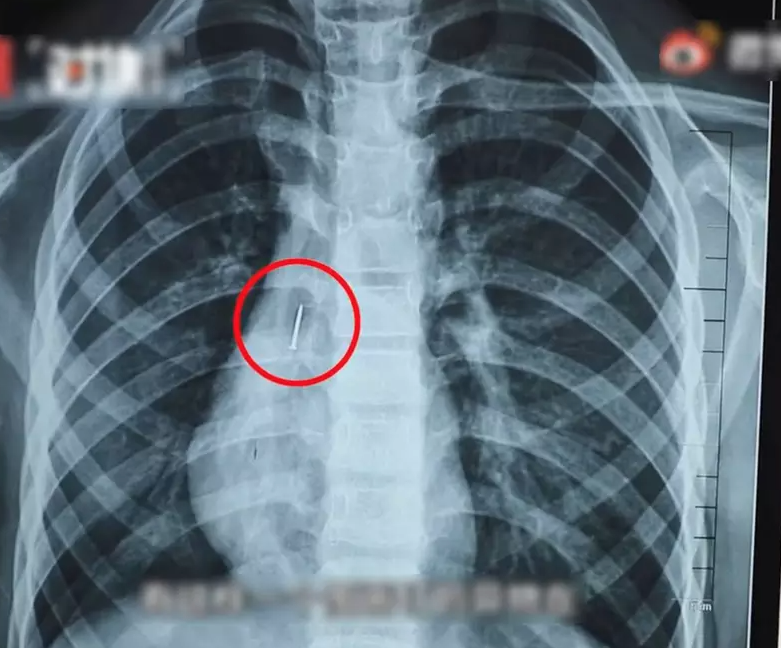

淮安市第一人民醫院醫生顧東升指出,小明入院後,團隊馬上為他進行支氣管鏡檢查,發現支氣管內的確有個圖釘狀的異物,被氣管內的軟骨環卡住,有可能堵住氣管,導致空氣進不去又出不來,造成缺氧而有生命危險。X光片無法顯示圖釘膠的部分,但見到整顆圖釘足足有3厘米長。